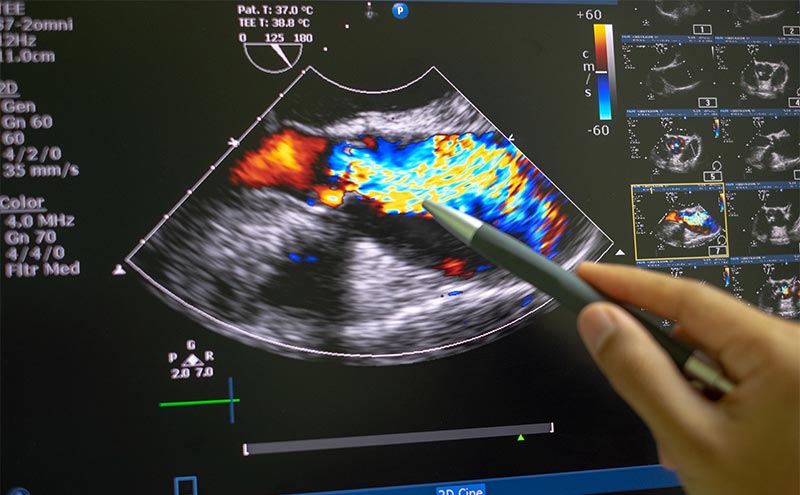

This is Mr. Youngblood’s take on the old adage “it’s better to be lucky than good,” because being consistently lucky requires first that you have thoroughly prepared with practice. What does this have to do with echocardiography (which I will henceforth abridge to “echo”) or ultrasound? Well, many practitioners of point-of-care ultrasound (POCUS), aside from training on basic knobology focused on depth and gain adjustment, have few opportunities to learn to troubleshoot their image acquisition. Novice sonographers hope to place the probe on the rough location of the body and strike sonographic gold. This is very true for echo, as the heart is a tremendously complicated organ that can only be visualized in two-dimensions, at any given time, by ultrasound. Being able to recognize the scan plane that you’re in, in relation to the 3D structure, and being able to predict which movements will yield the anticipated scan plane, takes significant dedicated practice. Recognizing this as the goal of echo is the crucial first step.

It doesn’t help that most instructional videos and texts on performing echo feature pristine echo images, with few actually tackling the issue of how to acquire and troubleshoot windows. It’s assumed that you already know these troubleshooting techniques, but there are few published guides on troubleshooting echo acquisition. My own experience learning echo was first in the ED, where I was taught by other residents and attendings to “put it here, and point here,” and essentially to work with the usually not optimal image obtained. My echo technique improved dramatically when I took an echo elective, where everyday for one month I learned and practiced with the cardiac sonographers. A seasoned cardiac sonographer is undeniably the best--and luckiest--practitioner in the room. But even after thousands of echos, they take the time to optimize their windows, because so much of what they do depends on the correct scan plane, insonation angle, and time frame. For example, EPSS should be done with the scan plane in the center of the left ventricle, with an insonation angle perpendicular to the interventricular septum, and measured during early diastole. Even subtle alterations in any of these variables will often lead to dramatically different measurements.

In emergency medicine, one rarely has more than 5-10 minutes to perform a POCUS study, so planimetry, in addition to its many limitations, is simply not time-effective. But that doesn’t mean that spending the time to improve image acquisition is not worthwhile. In fact, learning to recognize suboptimal images and the techniques to correct them consistently, saves time. But it requires that learners adopt this deliberate approach of understanding how the scan plane is slicing through the three-dimensional heart, and which movements are needed to obtain the correct image. I have distilled down my experience over hundreds of bedside echo teaching sessions to develop this simple approach to echo. (https://youtu.be/1mhitYUiAbI)1 In this first of a two-part series, we will go over this six-step process. This method focuses initially on obtaining the parasternal long axis window. Mastery of this view should help in obtaining the parasternal short axis and apical 4 chamber windows.